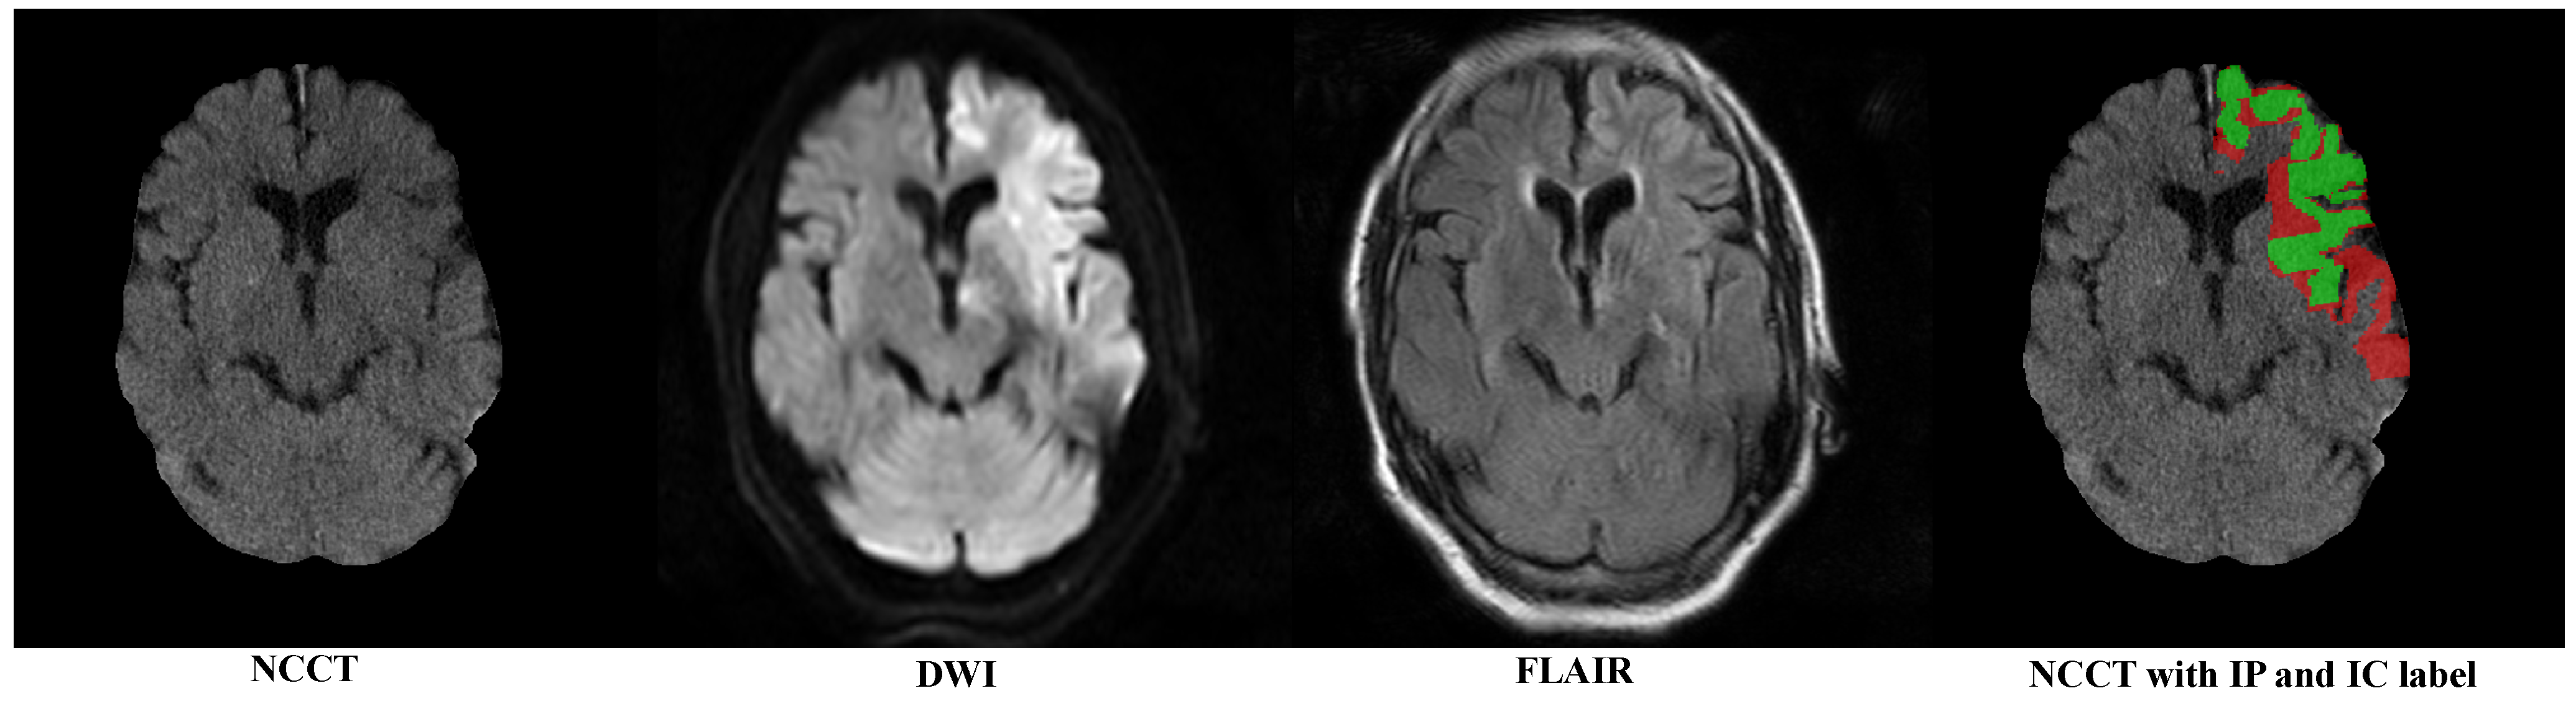

To eliminate the influence of the skull region, we first removed the skull following the method proposed by Najm et al. [24]. Figure 1 sequentially displays the NCCT after the skull removal, DWI with highlighted infarct signals, FLAIR showing a mismatch with DWI and the category labels for the IP (red) and IC (green).

Figure 1. An example of multi-modal image of a patient; DWI and FLAIR are registered to NCCT. The red and green regions represent the manually annotated IP and IC, respectively.